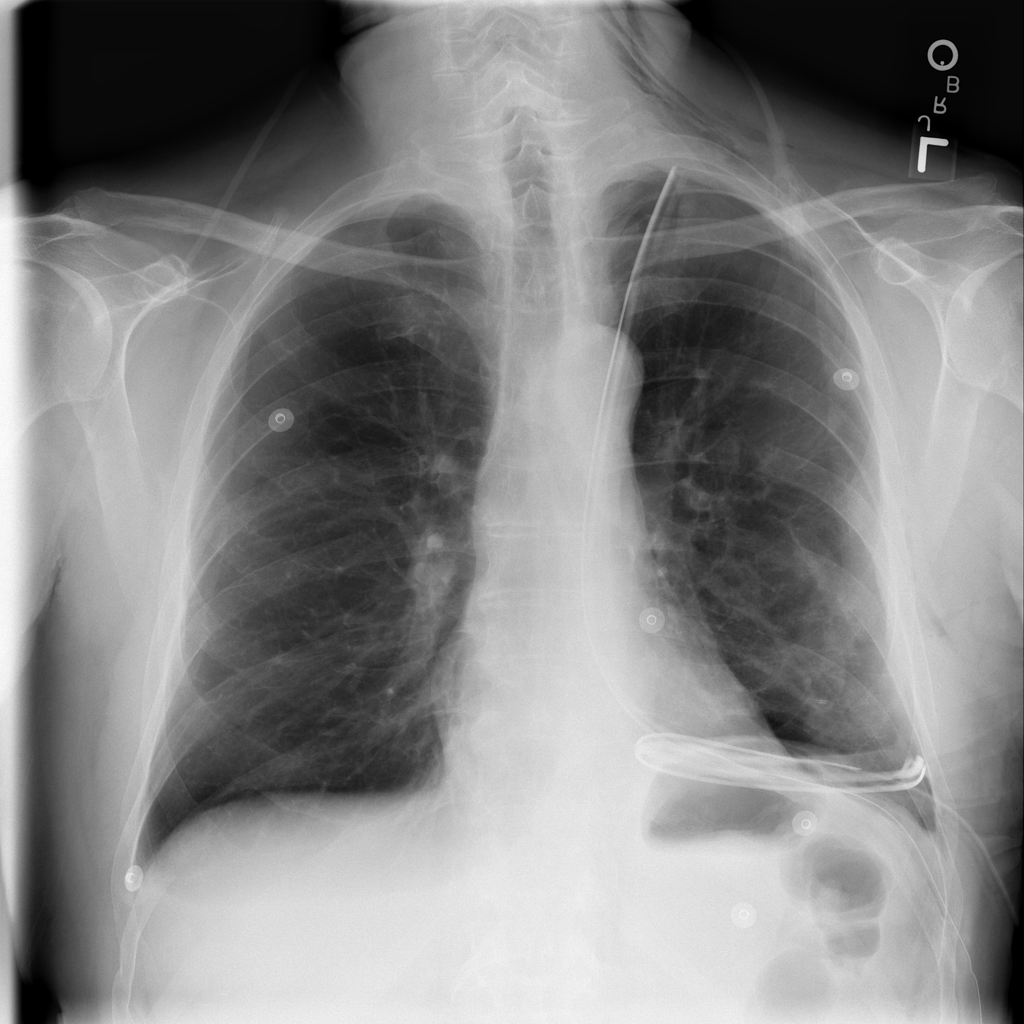

PAT-C255 · IMG-000Emphysema

PAT-C255 · IMG-000

PA